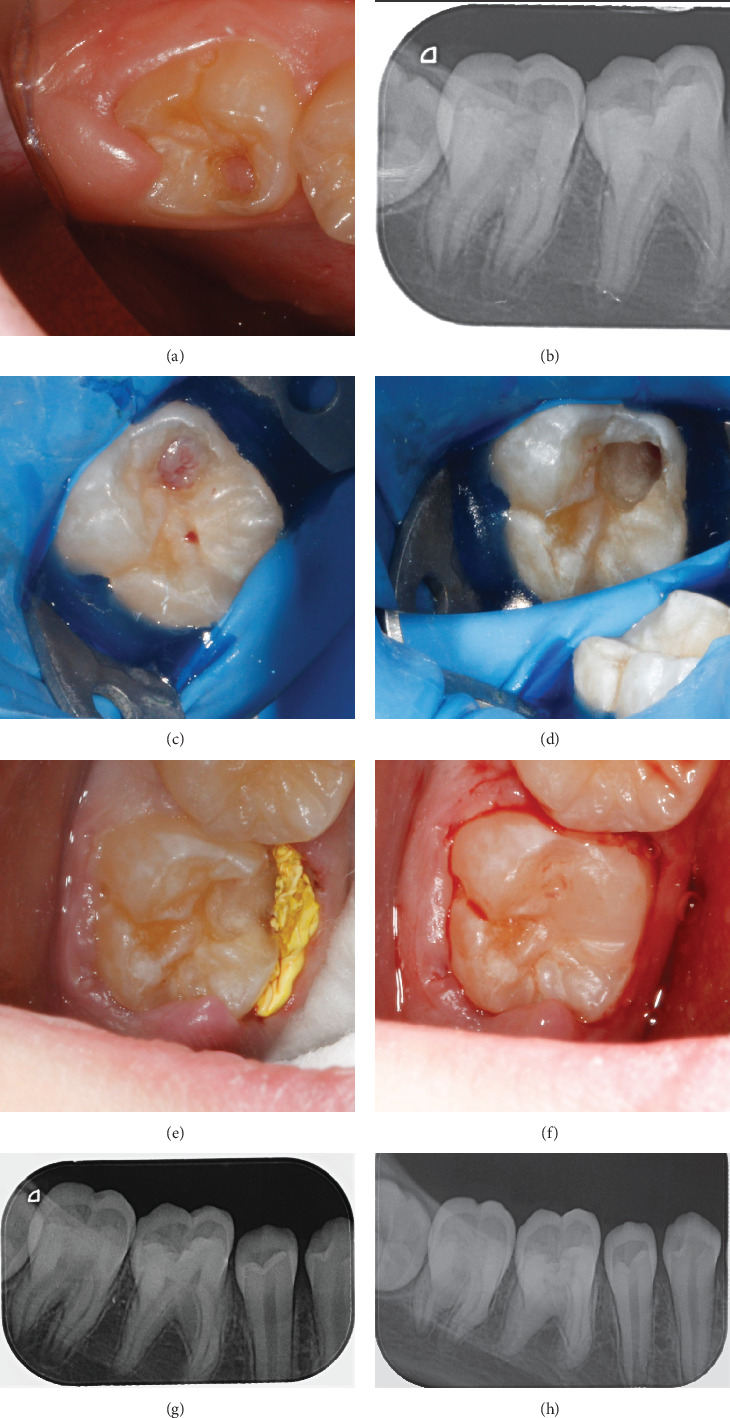

Intracoronal resorption (IR) is a condition characterized by the presence of lesions in the dentin of unerupted or erupting teeth, usually located just below the enamel-dentin junction in the occlusal part of the crown. This article presents two cases of IR-one with and one without pulp involvement. In both cases, the teeth were asymptomatic, and the lesions were discovered during routine checkups. The first case presents pre-eruptive IR with pulp involvement in an immature mandibular molar. To preserve the vitality of the growth zone and complete root development, vital pulp therapy was performed through total coronal pulpotomy and application of Biodentine. The second case is also of a mandibular molar with incomplete root development, but although it initially resembled invasive cervical resorption, treatment revealed that the granulation tissue was surrounded by intact enamel and did not affect the pulp or root of the tooth. No carious lesion was found. The tooth was conventionally restored with a composite filling.